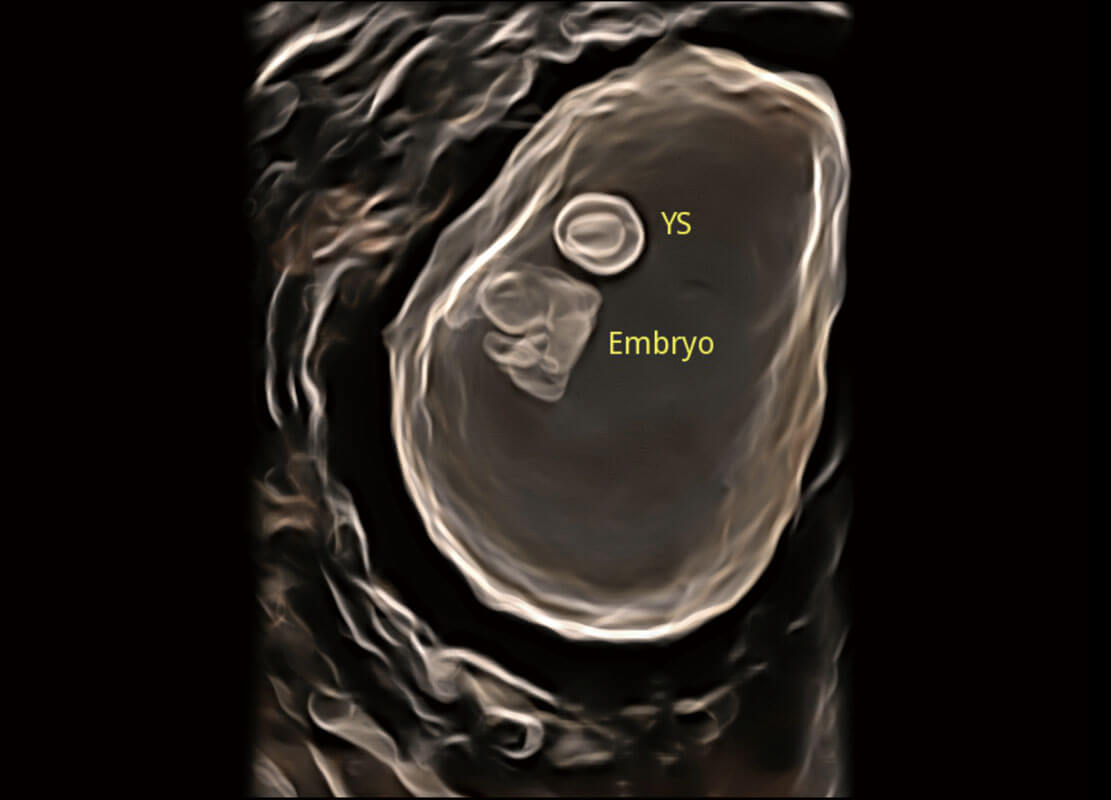

P60在胎儿早孕期超声筛查中为您带来优异的图像质量。

光影成像-孕囊